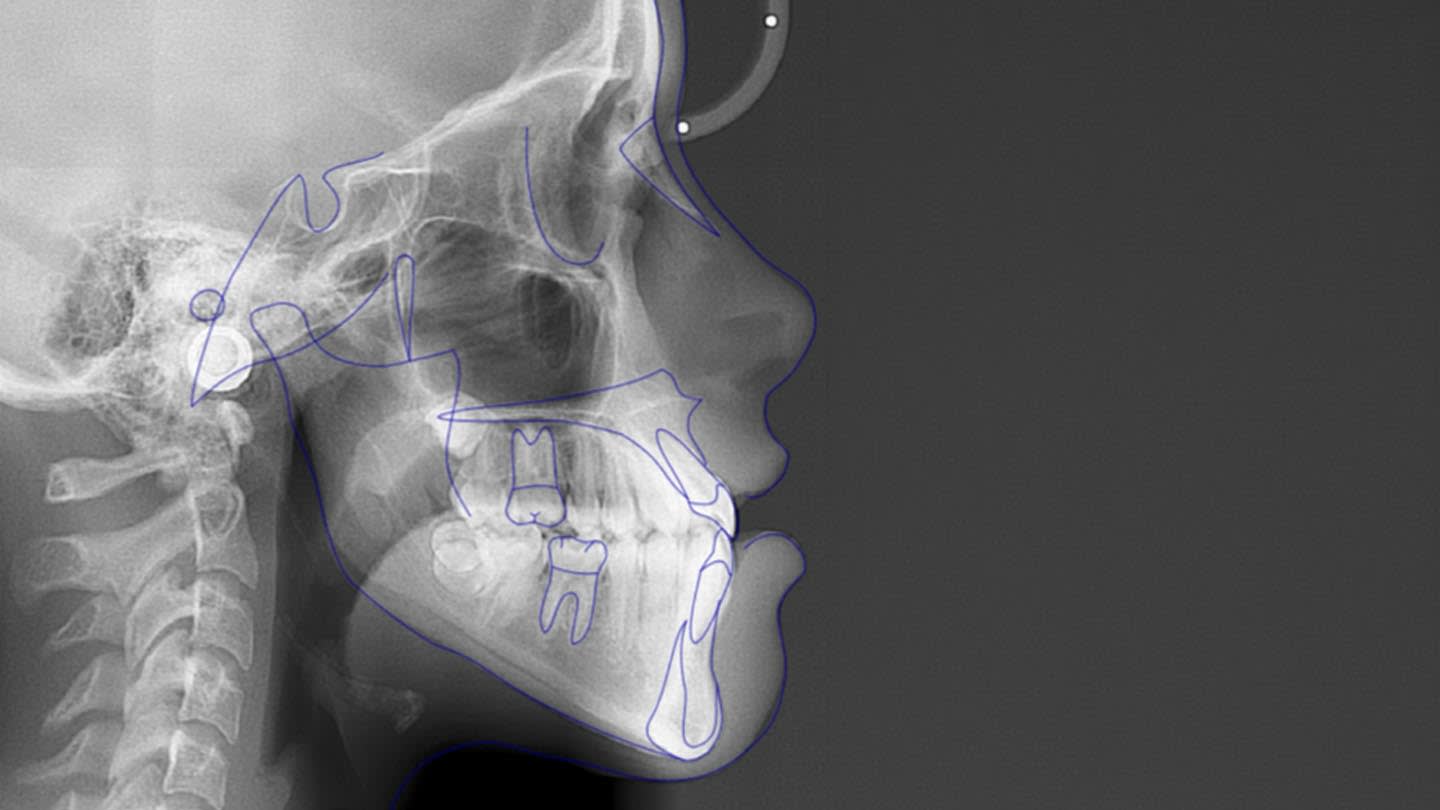

Despite variability in appliance design, all studies reported favorable outcomes with skeletal expanders for addressing transverse deficiencies in young adults. A case presentation illustrating treatment in a 16-year-old patient is shown in Figure 2 through Figure 39. (An additional case presentation may be viewed at compendiumlive.com/go/cced2110.) The studies also agree on the importance of individualizing miniscrew length and diameter in each case.25,26,30-32,34